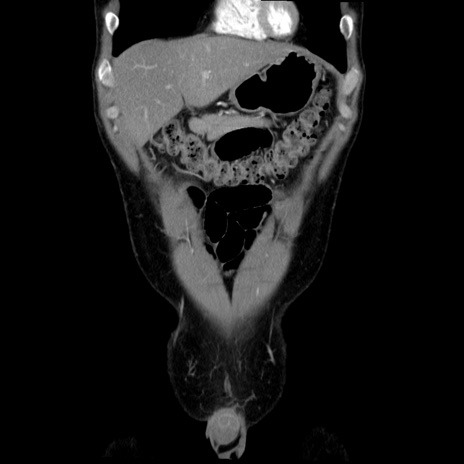

症例36(冠状断像)

【症例】20歳代 男性

【主訴】心窩部痛

【現病歴】今朝より上腹部痛あり。一旦軽快していたが再度出現したため救急要請。昨日夕に白身の魚を含む刺身を食べた。

【身体所見】BP 136/89mmHg、HR 74/min、BT 37.0℃、腹部:膨満、軟、心窩部に圧痛あり。反跳痛なし、筋性防御なし、腸雑音やや亢進あり。

【データ】WBC 17700、CRP 0.48